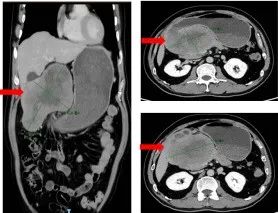

甲胎蛋白高达1737ng/m,但影像学表现不像肝癌,结合胃镜考虑肝样胃腺癌的可能”、“患者高龄,多个脏器生理储备功能下降,肿瘤巨大,包绕周边重要脏器,已出现周围淋巴结转移,建议免疫联合化疗后再考虑手术”……类似这些MD... |